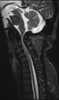

Hunter syndrome, or mucopolysaccharidosis type II (MPS II), is a rare genetic disorder in which large sugar molecules called glycosaminoglycans (or GAGs or mucopolysaccharides) build up in body tissues. It is a form of lysosomal storage disease. [Source: Wikipedia ]